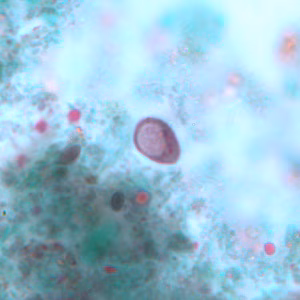

A ten-year-old child returned from summer camp with abdominal discomfort, nausea and diarrhea. He was taken to his pediatrician and a stool specimen was collected for routine work-up, including ova and parasite (O&P) examination. Figures A–D show what was observed on a trichrome-stained slide prepared from a PVA-preserved aliquot of the stool. The objects in Figures A and B measured approximately 11 micrometers; the objects in Figures C and D measured approximately seven micrometers. What is your diagnosis? Based on what criteria?

Figure A